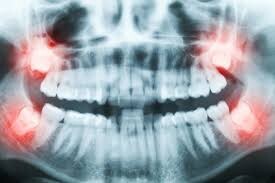

Conducting dental X-rays – These will be conducted to examine your dental structure and detect if there is any bone loss in the areas your dentist has detected any deeper pockets.

Wisdom teeth are your third set of molars set far back in the mouth. They develop when you’re between the ages of 17 and 25. When the wisdom teeth cause pain and/or are impacted, it’s recommended to get them removed. Let’s look at how these teeth came into being in the first place and what will happen if you need them removed.

Even if the wisdom tooth causes no symptoms, your dentist may recommend removal to prevent further damage or decay. The wisdom tooth will need to be extracted if it is impacted. An impacted wisdom tooth means the tooth is growing in at an odd angle that could affect nearby teeth or that the tooth sits along or within the jawbone.